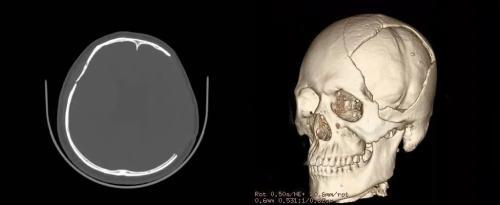

顱骨修補術前

PEEK顱骨修補產品通常在影像學檢查中表現良好,具有較好的影像兼容性。這意味著在X射線、計算機斷層掃描(CT)、磁共振成像(MRI)等醫學影像檢查中,PEEK顱骨植入物通常不會引起顯著的偽影或影響圖像的清晰度。對于患者術后復查以及其他疾病的診療有著重要的作用。

術后復查無偽影

顱骨修補術后復查